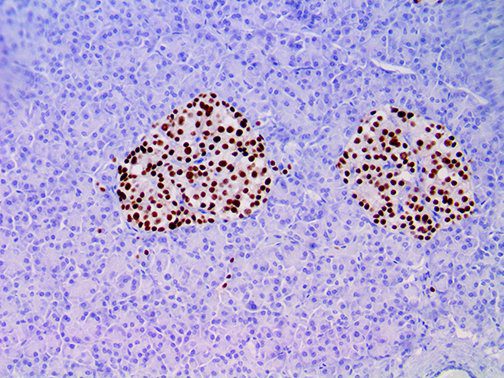

It is the ICU physician who is most likely to witness one of the deadliest manifestations of the abnormal immunological response, the cytokine storm syndrome (CSS). This response is also referred to by some as the cytokine release syndrome (CRS). CSS is characterized by continuous activation and expansion of macrophage and lymphocyte populations, which secrete large amounts of cytokines, causing the cytokine storm. This massive cytokine release is akin to hemophagocytic lymphohistiocytosis (HLH) disease, a syndrome characterized by initial unchecked and persistent activation of cytotoxic T lymphocytes and NK cells.

Clinical and laboratory manifestations of HLH include fever, enlarged liver and/or spleen, neurologic dysfunction, coagulopathy, liver dysfunction, cytopenias (i.e., low levels of erythrocytes, leukocytes, and/or platelets), hypertriglyceridemia, hyperferritinemia, hemophagocytosis, and eventually diminished NK cell activity as the immune system becomes progressively paralyzed. HLH can be familial (primary HLH) or secondary to another disease process (sHLH), such as rheumatic disease, in which it is referred to as macrophage activation syndrome (MAS, characterized by elevated ferritin).